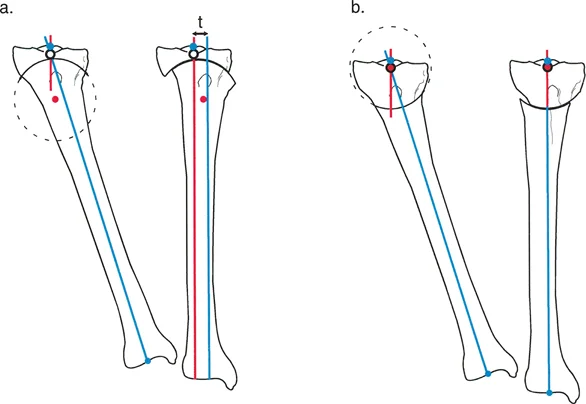

قطع العظم القبة المتقدم (Dome Osteotomy)

يُعد قطع العظم القبة بديلاً متقدمًا لتقنيات القطع المستقيمة التقليدية. على الرغم من أن كلمة "قبة" تشير عادة إلى سطح كروي، إلا أنها في جراحة العظام تعني قطعًا أسطوانيًا الشكل في العظم ثلاثي الأبعاد. هذا النوع من القطع يمنح الجراح مرونة ودقة لا مثيل لهما في تصحيح التشوهات.

مزايا قطع العظم القبة للمريض:

- قابلية التعديل اللانهائية: يسمح القطع الأسطواني لأطراف العظم بالانزلاق بسلاسة على طول قوس، مما يتيح تعديلات دقيقة للغاية أثناء الجراحة في المستويين الأمامي والخلفي أو الجانبي. هذا يعني أن الجراح يمكنه تحقيق المحاذاة المثالية.

- أقصى تلامس بين العظام: على عكس قطع العظم بالوتد المفتوح الذي يخلق فجوة تتطلب ترقيعًا، أو قطع العظم بالوتد المغلق الذي يقصر الطرف، يحافظ قطع العظم القبة على مساحة تلامس كبيرة بين أسطح العظم، مما يعزز التئام العظم الأولي السريع.

- استقرار طبيعي: توفر الأسطح الأسطوانية المتطابقة استقرارًا داخليًا ممتازًا ضد الانزلاق، مما يجعل تثبيت الأدوات الجراحية (مثل المثبتات الخارجية أو الألواح) أكثر موثوقية وأمانًا.

- لا يوجد فقدان للعظم: يمكن أن يحقق هذا القطع تأثير الوتد المغلق دون الحاجة إلى إزالة قطعة عظمية فعلية، مما يحافظ على طول الطرف.

تحديات قطع العظم القبة:

- صعوبة تقنية: يتطلب عمل قطع أسطواني مثالي مهارة جراحية فائقة ودقة عالية، وغالبًا ما يستخدم الجراح سلسلة من الثقوب المتوازية المتصلة بمشرط منحني، أو شفرات منشار دائرية متخصصة.

- عدم التوافق مع تصحيح الدوران: نظرًا لأن القطع أسطواني، فإن محاولة تدوير الجزء البعيد من العظم (في المستوى المستعرض) ستؤدي إلى عدم تطابق الأسطح وتكوين فجوة، مما يسبب عدم الاستقرار وفقدان تلامس العظم.

- تناقص التلامس مع الأقواس الكبيرة: كلما زاد نصف قطر قطع العظم الدائري، أصبح القوس أكثر تسطحًا. مع التصحيحات الزاوية الكبيرة، يؤدي نصف القطر الكبير إلى تناقص تلامس العظم. لذلك، فإن قطع العظم القبة يكون عمليًا أكثر في مناطق الكردوس حيث يكون قطر العظم أوسع، مما يسمح بنصف قطر أكثر إحكامًا.